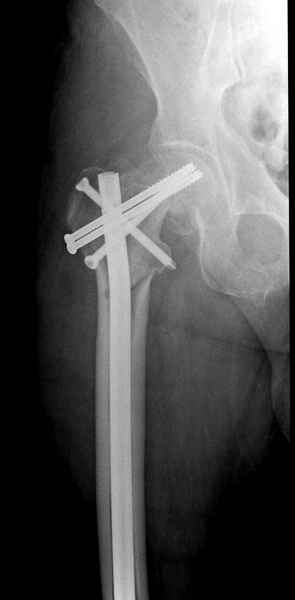

На второй день после выписки упал дома. Снимки приложены. Коллеги рекомендуют удаление шурупа и вытяжение. Что делать?

Привет из солнечного Будапешта с Eurotrauma-2008. Да, замечательный пример. Получается, профилактику расхождения отломков шейки надо было проводить каким-то реконструкционным или проксимальным гвоздем, причем сразу длинной версией. Сейчас, наверно, так и надо бы сделать.

Убрать винты, каким-то джойстиком в вертельной области сделать репозицию шейки, фиксировать ее спицами, а дальше вправлять и фиксировать как вертельный перелом.

Решайте проблемы по мере поступления. На первом этапе решение одно, и на мой взгляд верное. Ситуация изменилась кардинально - другое решение. Я бы избрал ресинтез, убрав винты заменил на Гамму. Что с ним будет послезавтра? - Будем решать послезавтра. Такая наша доля.

"Решайте проблемы по мере поступления. На первом этапе решение одно, и на мой взгляд верное. Ситуация изменилась кардинально - другое решение. Я бы избрал ресинтез, убрав винты заменил на Гамму. Что с ним будет послезавтра? - Будем решать послезавтра. Такая наша доля."

Правильно, ситуация изменилась, как говорят у нас теперь "different animal", надо решать проблему подвертельного перелома. При наличии различных вариантов фиксаторов, включая Страйкер Гамма 3, мы выбрали DePuy Antegrade Trachanteric Nail из-за многовариантности проксимальной фиксации и двойного изгиба. Вводится через вертел под 8 градусным углом, и есть достаточный передний диафизарный изгиб, предупреждающий пенетрацию дистального переднего кортекса.

Кто знает что дальше, мысленно готовы к проксимальной артропластике.

Но ведь и головка бедра сползла в варус - отчего ограничились только фиксацией подвертельного перелома, а не убрали винты и не сделали репозицию шейки?